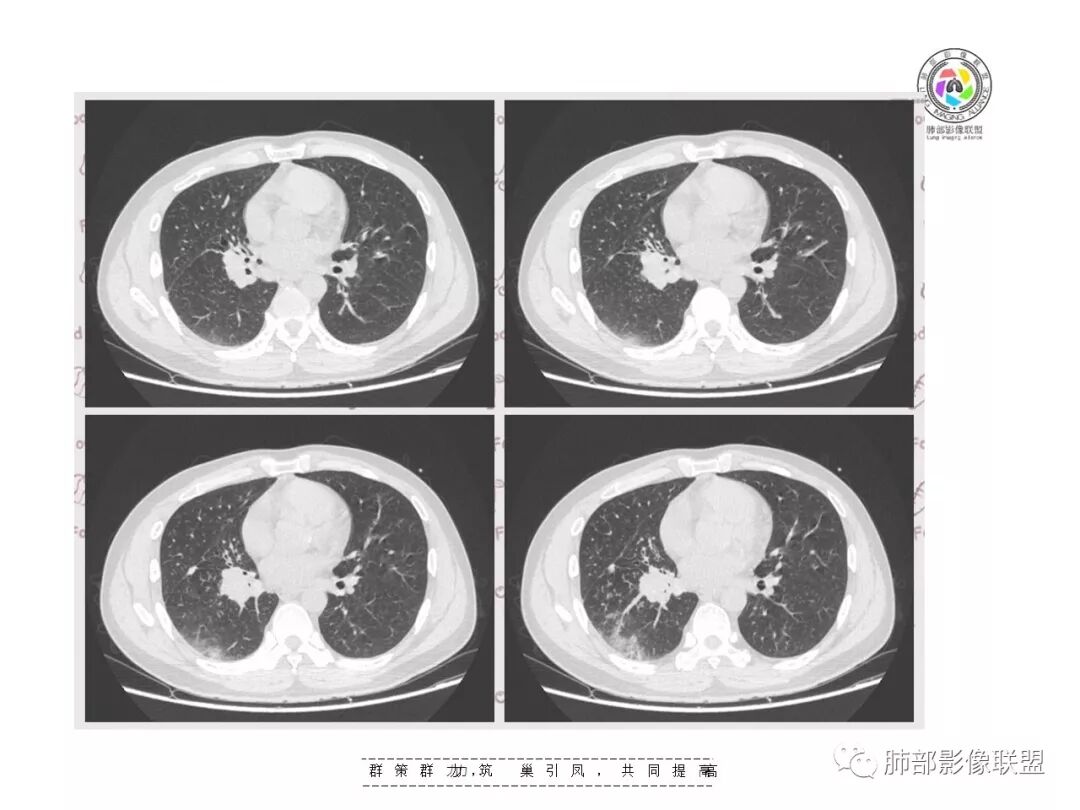

【影像资料】

下叶外基底段为主实变,周围GGO

分布:沿支气管段、亚段朝外蔓延分布

实变区边缘收缩,支气管走形自然

GGO边界大部分不清楚,内有树芽征,中央间质均匀增厚

如果单独讨论这个病灶:我倾向于急性感染性病变

因为病灶的分布就是沿支气管走形,病灶整体就是沿段分布

实变区边界清、凹陷及平直,内部密度均匀,强化均匀,支气管在密实处填塞,其余部分通畅、走形自然,中央间质均匀增厚

GGO均匀,边界模糊,树芽征

但是这个病例是由支气管往下,越来越淡,与支气管是平行走形,然后支气管壁增厚,还有树丫,虽然带着GGO的,分布属于支气管往下来的,这个和粘液腺癌不同,和肺炎链球菌也不同。比较符合TB,支原体这些。